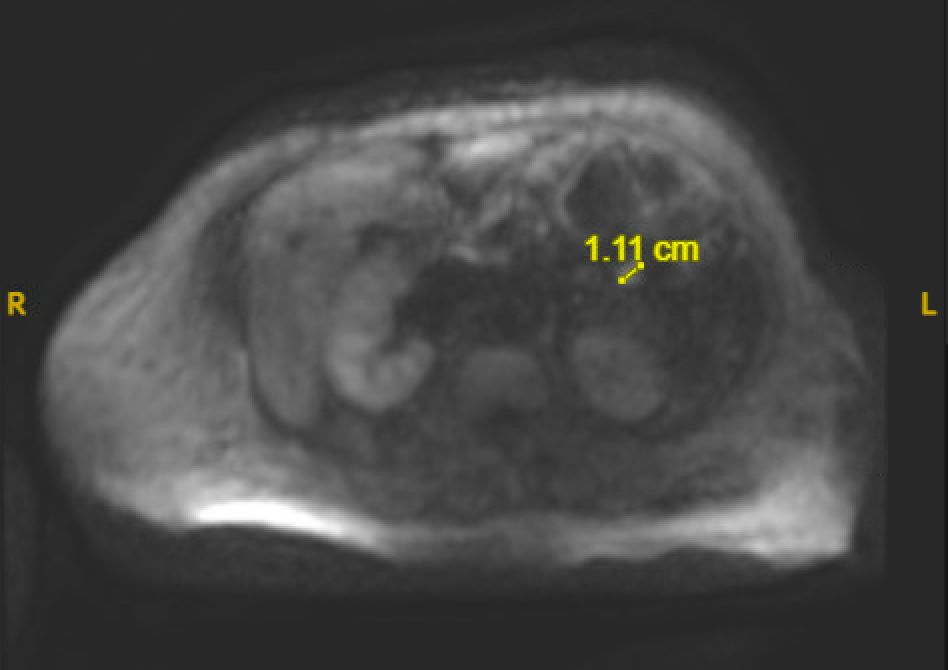

Case Presentation: A 63-year-old female with a history of heart failure with reduced ejection fraction and pre-diabetes presented to the hospital with lower extremity weakness. On presentation, her physical exam was significant for bilateral lower extremity pitting edema and hepatomegaly. Lab work showed an elevated total bilirubin (7.3mg/dL) and direct bilirubin (3.8mg/dL), liver function tests (AST 675, ALT 493), and brain natriuretic peptide (1397.3pg/mL). She was admitted for treatment of heart failure exacerbation as well as for workup of her acute liver injury. During her hospital admission, she had several episodes of symptomatic hypoglycemia characterized by feeling weak and tremulous with venous glucose < 40mg/dL. Her symptoms improved with dextrose infusions. Further work up revealed an elevated C-peptide (8.6ng/mL), inappropriately normal insulin level (3.4μU/mL), proinsulin (6.8pmol/L), low insulin-like growth factor-2, negative insulin antibody, A1c of 5.7%. A CT of her abdomen/pelvis and later an MRI with Eovist contrast revealed a 1.1cm lesion in the proximal jejunum concerning for an insulin-secreting neuroendocrine tumor or gastroenterological stromal tumor. Other causes of hypoglycemia were ruled out as her symptoms persisted despite adequate nutrition, treatment of her heart failure, and improvement in her liver function to AST 55, ALT 31, total bilirubin 3.8mg/dL. Her blood alcohol level and cortisol were normal, and all drugs and medications side effects were ruled out including a negative sulfonylurea screen. The patient was treated with Octreotide, dextrose gel, and Glucerna shakes with improvement in her symptoms and venous glucose. On discharge, she had achieved normoglycemia but was given close follow up with Endocrinology and scheduled for a PET scan for further evaluation for metastatic disease.